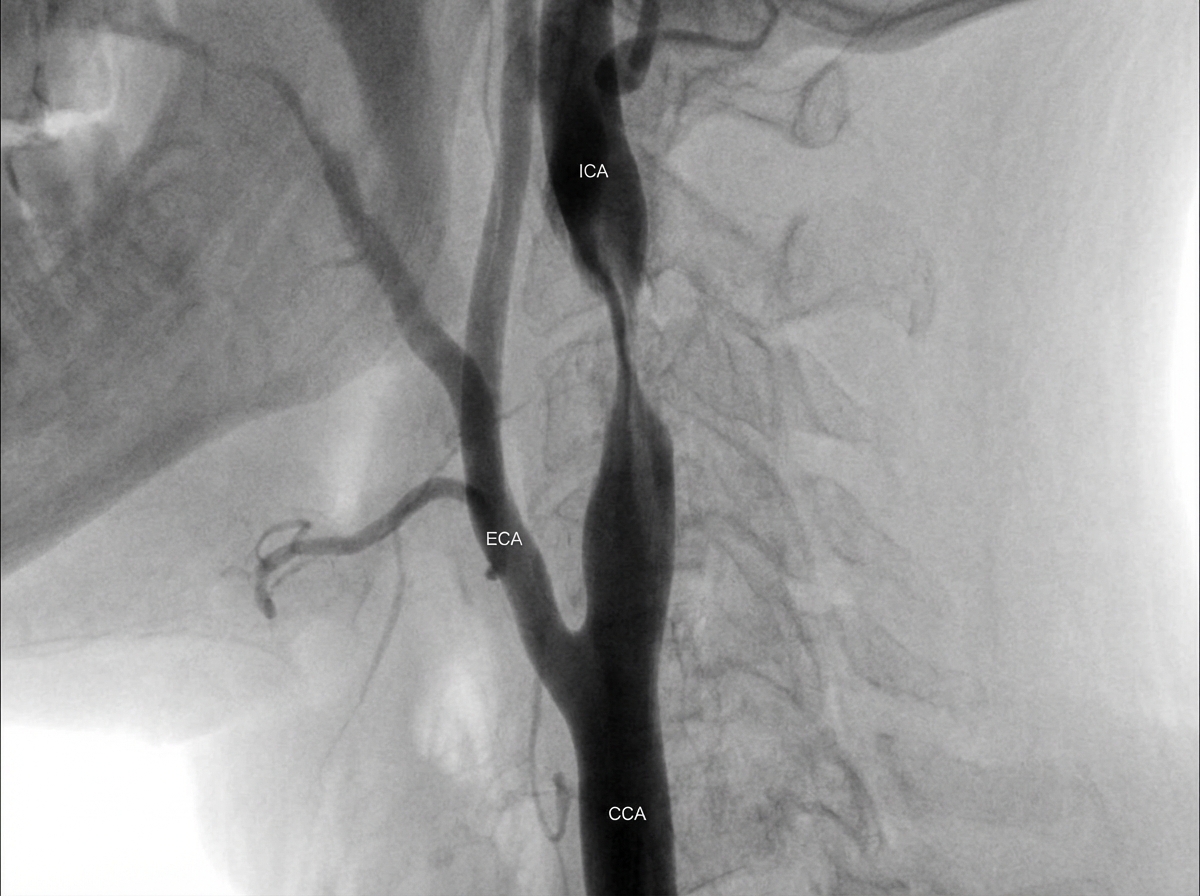

An arteriogram of a 75-year-old man with an asymptomatic carotid bruit, mild hypertension, and mild COPD is shown. What is the current recommended management for this patient?

Explanation: ***Carotid endarterectomy*** - **ACAS trial** evidence shows **CEA** reduces stroke risk by **53%** in asymptomatic patients with **≥60% stenosis** who have life expectancy >5 years. - **Mild COPD** and **mild hypertension** are not contraindications to CEA in a 75-year-old with good functional status. *Medical therapy with aspirin 325 mg/day and medical risk factor management* - While **antiplatelet therapy** is important, aspirin alone is **insufficient** for significant asymptomatic carotid stenosis (≥60-70%). - Medical management alone has **higher stroke risk** compared to CEA plus medical therapy in appropriate surgical candidates. *Medical therapy with warfarin* - **Warfarin** is not indicated for **carotid artery stenosis** and does not reduce stroke risk in this condition. - **Anticoagulation** carries **bleeding risks** without proven benefit for atherosclerotic carotid disease. *Angioplasty of the carotid lesion followed by carotid endarterectomy if the angioplasty is unsuccessful* - **Carotid angioplasty** is typically reserved for **high-risk surgical candidates** or hostile neck anatomy. - **CEA remains gold standard** for asymptomatic stenosis in good surgical candidates based on **superior long-term outcomes**.

Explanation: **Explanation:** **1. Why Option D is Correct:** Aspirin is a cornerstone in the medical management of carotid artery disease. It acts as an antiplatelet agent by irreversibly inhibiting cyclooxygenase-1 (COX-1), thereby preventing the formation of Thromboxane A2. Since most TIAs and strokes in carotid stenosis result from **micro-emboli** (platelet-fibrin aggregates) forming on the atherosclerotic plaque, aspirin significantly reduces the frequency of TIAs and the overall risk of ischemic stroke. **2. Why Other Options are Incorrect:** * **Option A:** This is a classic "lateralization" trap. Carotid stenosis causes **contralateral hemiplegia** (weakness on the opposite side of the lesion) because the motor fibers decussate in the medulla. While the embolism does often involve the Middle Cerebral Artery (MCA), the clinical deficit is seen on the opposite side. * **Option B:** A carotid bruit is a poor indicator of severity. While a bruit suggests turbulent flow, it may disappear entirely when stenosis becomes critical (e.g., >90% occlusion) because the flow volume becomes too low to generate sound. * **Option C:** Atherosclerosis most commonly affects the **Carotid Bulb** and the origin of the **Internal Carotid Artery (ICA)**, not the External Carotid Artery. **Clinical Pearls for NEET-PG:** * **Gold Standard Investigation:** Digital Subtraction Angiography (DSA); however, Duplex Ultrasound is the initial screening tool of choice. * **Surgical Threshold:** Carotid Endarterectomy (CEA) is generally indicated for symptomatic patients with **>50-70% stenosis** and asymptomatic patients with **>60% stenosis** (provided life expectancy is >5 years). * **Amaurosis Fugax:** Transient monocular blindness ("curtain falling") is a classic symptom of carotid disease due to emboli in the ophthalmic artery. Unlike hemiplegia, this symptom is **ipsilateral** to the stenosis.